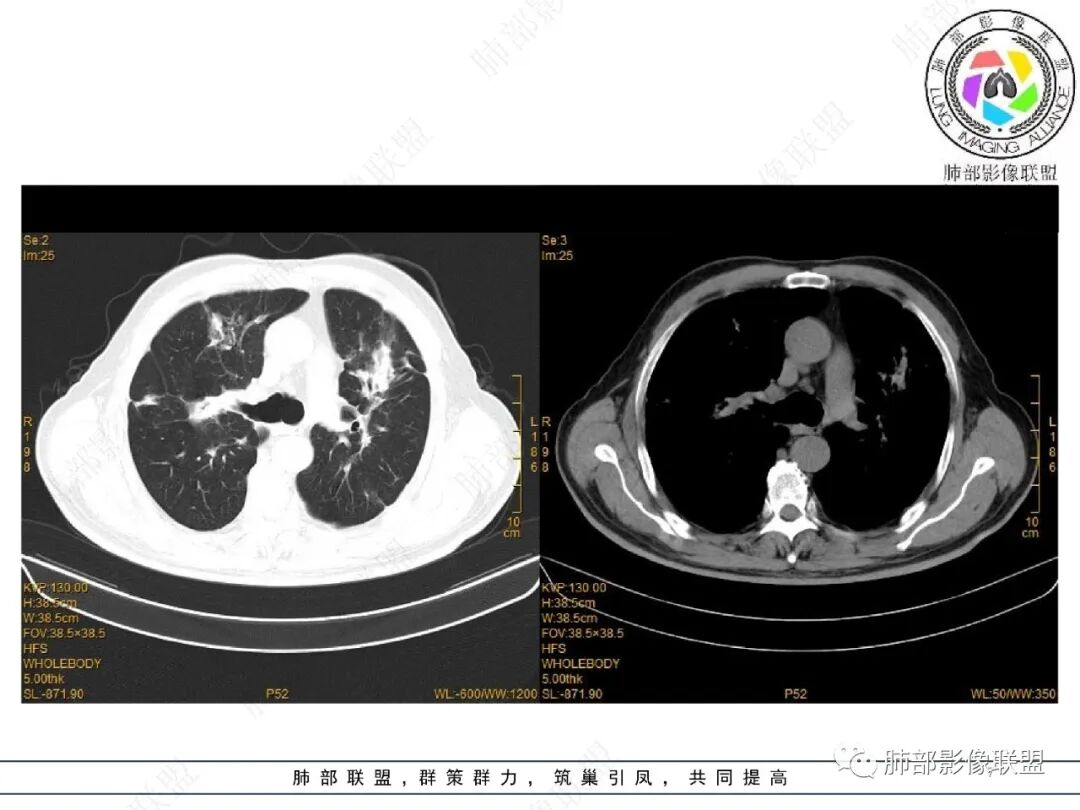

2022.2.17CT显示两肺中内带多发结节影、斑片影、条索影,部分病灶侧向融合与胸膜平行。部分病灶沿着支气管血管束分布、其内支气管稍扩张。部分病灶呈反晕征。大部分病灶边界显示清晰,部分病灶周围可见边界不清的GGO。2022.4.12CT显示两肺中内带多发结节影、条索状、条带状高密度影,边界收缩平直凹陷,大部分病灶沿着支气管血管束分布,亦有位于胸膜下侧向融合与胸膜平行的病灶。总体与第一次CT对比两肺病灶明显吸收。